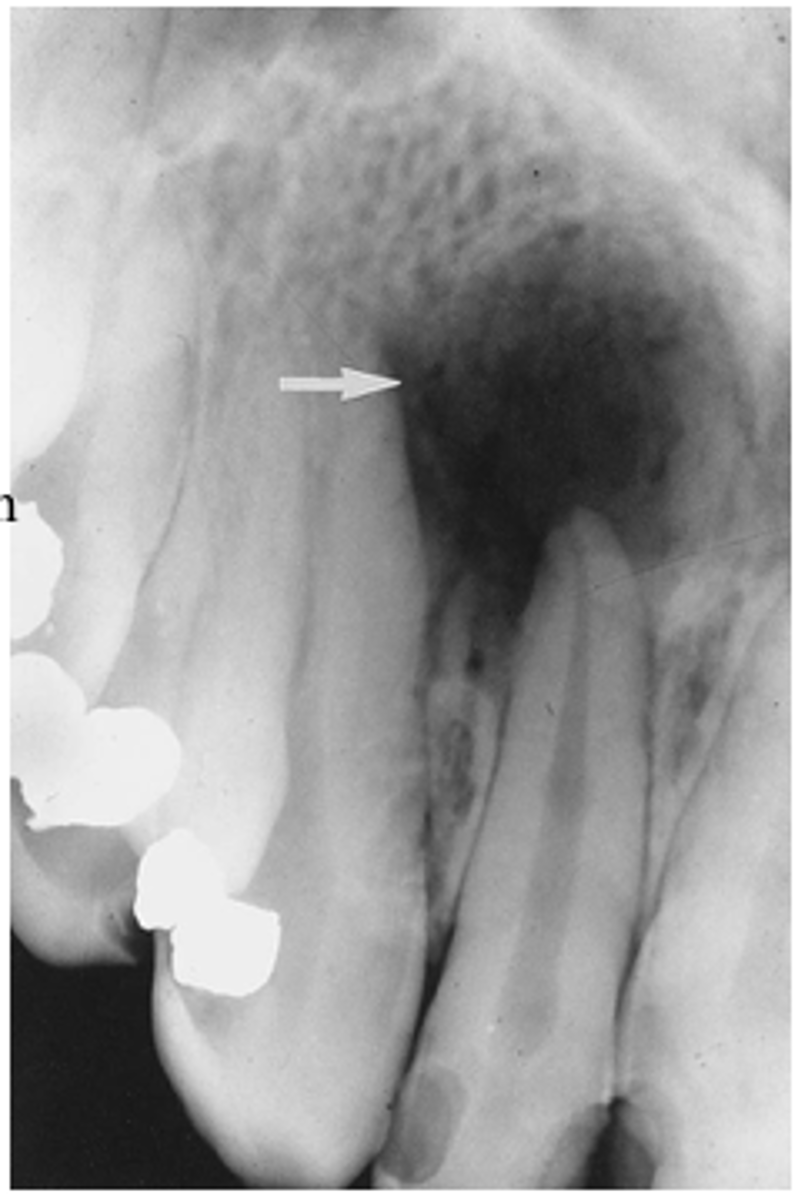

What are radiographic features of adenomatoid odontogenic tumors?

unilocular radiolucency with opaque flecks - "snowflakes"

What is the treatment and prognosis of an adenomatoid odontogenic tumor?

⢠treatment: surgical removal

⢠prognosis: excellent - no recurrence